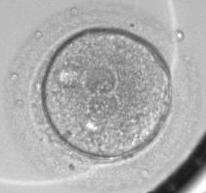

PORTLAND, Ore. - Scientists at Oregon Health & Science University, Stanford University, University of Valencia and IGENOMIX have discovered that chromosomal abnormalities in human embryos created for in vitro fertilization, or IVF, can be predicted within the first 30 hours of development at the cell-1 stage which results from the union of a female egg and male sperm.

This discovery, published online today in the journal Nature Communications , could improve IVF success rates, which has hovered around 30 to 35 percent for numerous years worldwide. It is estimated that between 50 to 80 percent of embryos created for IVF have a chromosomal abnormality and typically do not develop into a pregnancy, instead resulting in a miscarriage.

Key findings of this research, which was conducted by Shawn L. Chavez, Ph.D. and her colleagues at Stanford University and analyzed at OHSU, showed that by looking at the duration of the first mitotic phase - a short period in the cell cycle - one can identify chromosomally normal versus abnormal embryos up to approximately the 8-cell stage. Most importantly, by looking at a single cell level, researchers were able to correlate the chromosomal make-up of an embryo to a subset of 12 genes that are activated prior to the first cell division. These genes likely came from the gametes - the eggs or sperm - and can be used to predict whether an embryo is chromosomally normal or abnormal at the earliest stage of human development.

This research was conducted using 117 human zygotes originating from 19 couples, with an average maternal age of 33.7 ± 4.3 years. Researchers obtained this large set of human embryos from previous IVF cycles after written informed consent from the Stanford University RENEW Biobank. Through single cell gene expression profiling - the measurement of the activity of hundreds of genes at once - Chavez and colleagues identified a subset of developmentally relevant genes that are activated prior to the first cell division using computer-assisted mathematical modeling that can be used to predict whether the embryo is chromosomally normal or abnormal.